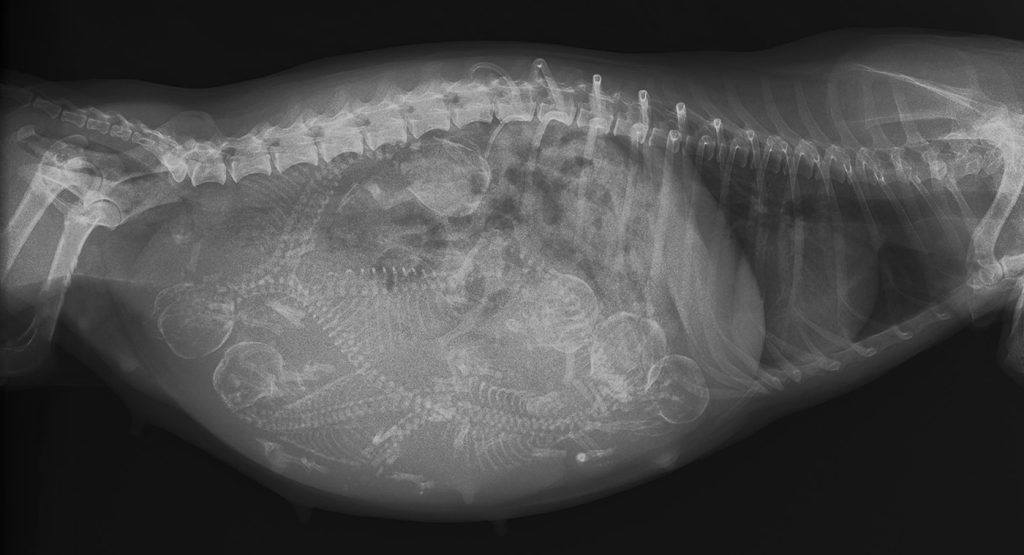

Bij drachtige teven kan mummificatie van de vruchten ontstaan, maar ook zien we vroeggeboorte, doodgeboren pups of zeer zwakke puppy’s.

De heftigheid van het Herpesvirus bij puppy’s hangt af van de leeftijd waarop het dier besmet wordt met het virus. Puppy’s jonger dan drie weken oud beginnen met sloomheid, hebben weinig eetlust, maar geen koorts en hebben luchtwegproblemen (benauwdheid, met open bek ademen). Ook kunnen ze een gespannen pijnlijke buik krijgen, gaan gillen en kunnen er ook bloedingen op de slijmvliezen ontwikkelen. Braken en een te zachte gelig grijze of groene ontlasting kunnen ook gezien worden. Het Herpesvirus plant zich snel voor en tast alle organen van de pup aan, wat resulteert in een snelle dood. Dit kan al 24 tot 72 uur na de eerste verschijnselen gebeuren. De puppy’s die het overleven kunnen op latere leeftijd problemen krijgen met de nieren, longen, hersenen of ogen.